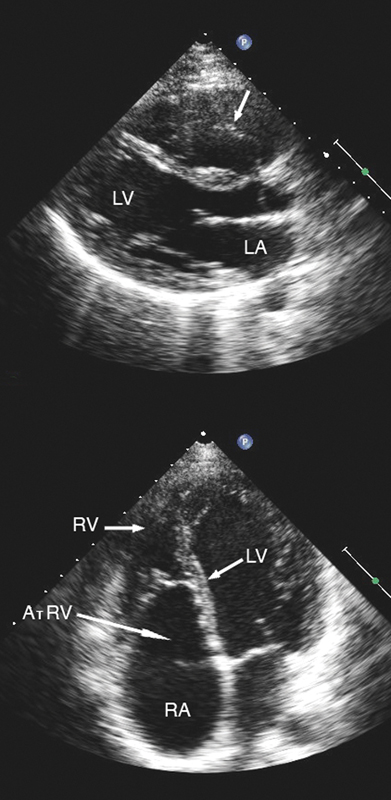

فحوصات تشخيصية لبعض امراض القلب والشرايين التاجية